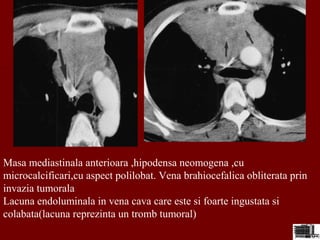

Masa mediastinala anterioara ,hipodensa neomogena ,cu

microcalcificari,cu aspect polilobat. Vena brahiocefalica obliterata prin

invazia tumorala

Lacuna endoluminala in vena cava care este si foarte ingustata si

colabata(lacuna reprezinta un tromb tumoral)